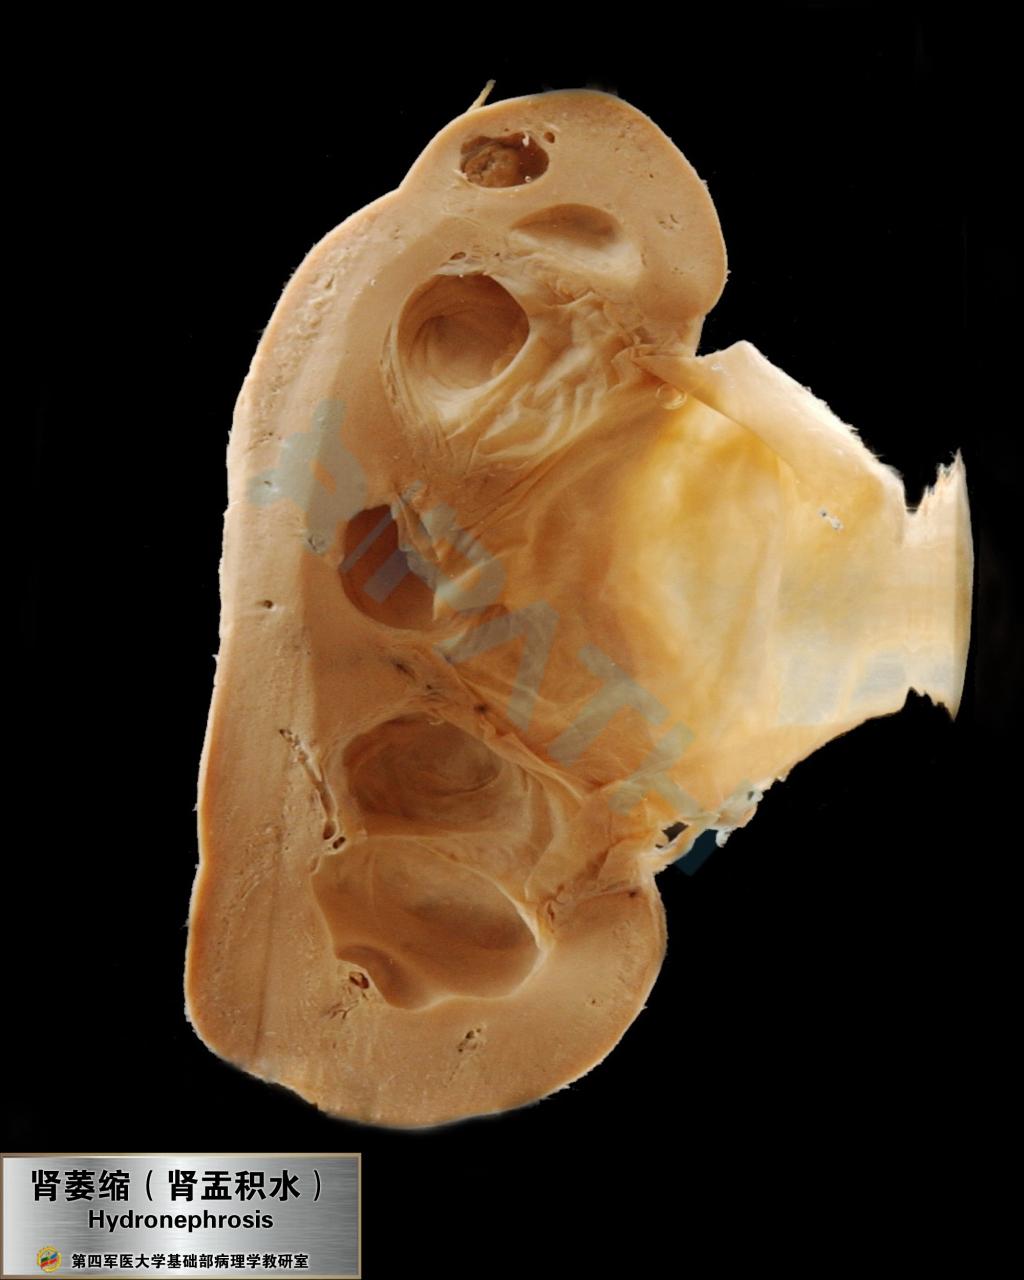

肾压迫性萎缩